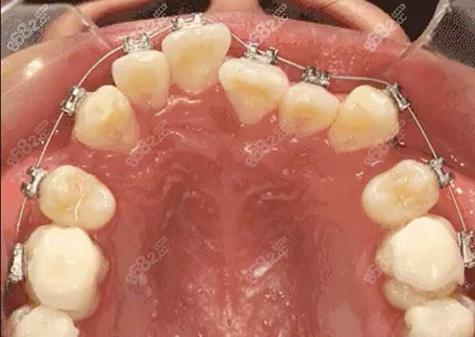

该院成立于2014年,位于荷塘区红旗南路1号,是株洲较早开展数字化正畸的专业机构。医院拥有汪银波、杨少伟等多名擅长牙齿矫正的医师团队,可开展金属托槽、隐形矫正等多种矫治技术,青少年早期干预矫正案例丰富,单颗托槽矫正价格约6800元起。

作为2012年成立的老牌口腔机构,天元店位于嵩山路8号,张晓医师领衔的正畸团队在复杂错颌畸形矫正方面经验突出。医院引进iTero口扫设备,可提供隐适美、时代天使等隐形矫正方案,全口隐形矫正价格约2.8万元起,保持器终身免费维护。

2020年成立的现代化口腔专科,位于太子路顺鑫佳园。龚赛花医师专注正畸领域10余年,尤其擅长青少年功能性矫正,采用MRC肌功能矫治器预防牙颌畸形发展,儿童早期干预费用约1.2万元起,含3次复诊跟踪调整。

徐家桥店作为2013年成立的综合口腔,由文树生副主任医师坐诊,采用DSD微笑设计配合正畸治疗。特色项目包括陶瓷半隐形矫正(1.5万元起)和自锁托槽矫正(9000元起),提供矫正前后3D模拟效果展示。

2020年成立的精品齿科,位于建设路千金文化广场。易勇主治医师团队擅长复杂病例的多学科联合治疗,将正畸与种植、修复相结合,全口矫正周期约18-24个月,分期付款可享9折优惠。